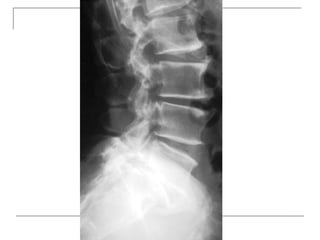

 Lateral

-fracture/wedging

-kyphosis

-spondylolisthesis

Plain x-rays